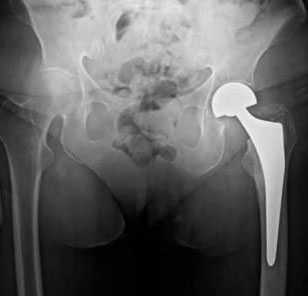

Рис.: Бесцементный тотальный эндопротез правого тазобедренного сустава, установленный в результате малоинвазивной операции по AMIS-технологии.

Бесцементный тотальный эндопротез правого тазобедренного сустава, установленный в результате малоинвазивной операции по AMIS-технологии.